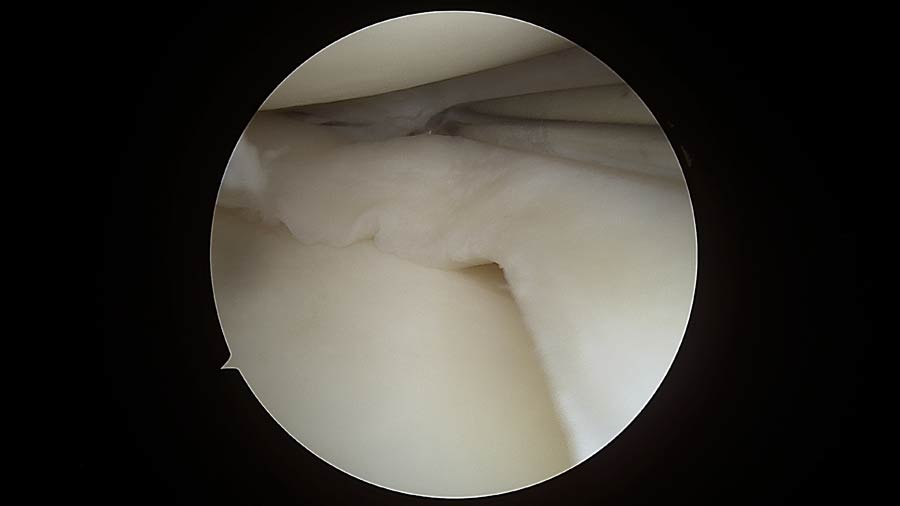

Lesioni meniscali: I menischi svolgono un ruolo essenziale nella protezione dell’articolazione. Una loro lesione può provocare dolore improvviso, blocchi articolari e limitazione funzionale. Attraverso procedure artroscopiche mini-invasive intervengo in modo preciso sulla parte danneggiata, riducendo i tempi di recupero e facilitando il ritorno alle normali attività quotidiane.